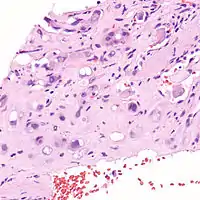

| Micrograph of an epithelioid hemangioendothelioma of the liver. | |